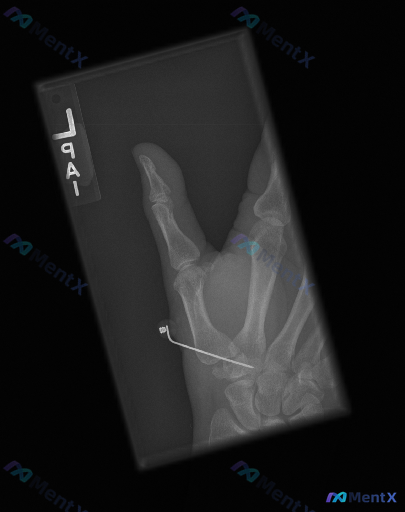

整理了一份左手拇指区域的斜位X光病例资料,先把客观影像表现放出来: - 可见左手拇指近节、远节指骨及第一掌骨,第一腕掌关节、掌指关节、指间关节对位尚可,关节间隙宽度尚可 - 第一掌骨桡侧近基底部区域有一枚金属克氏针影,穿过第一掌骨,针尾弯曲并带有固定装置,从皮下穿出或止于皮下软组织层 - 克氏针穿行...